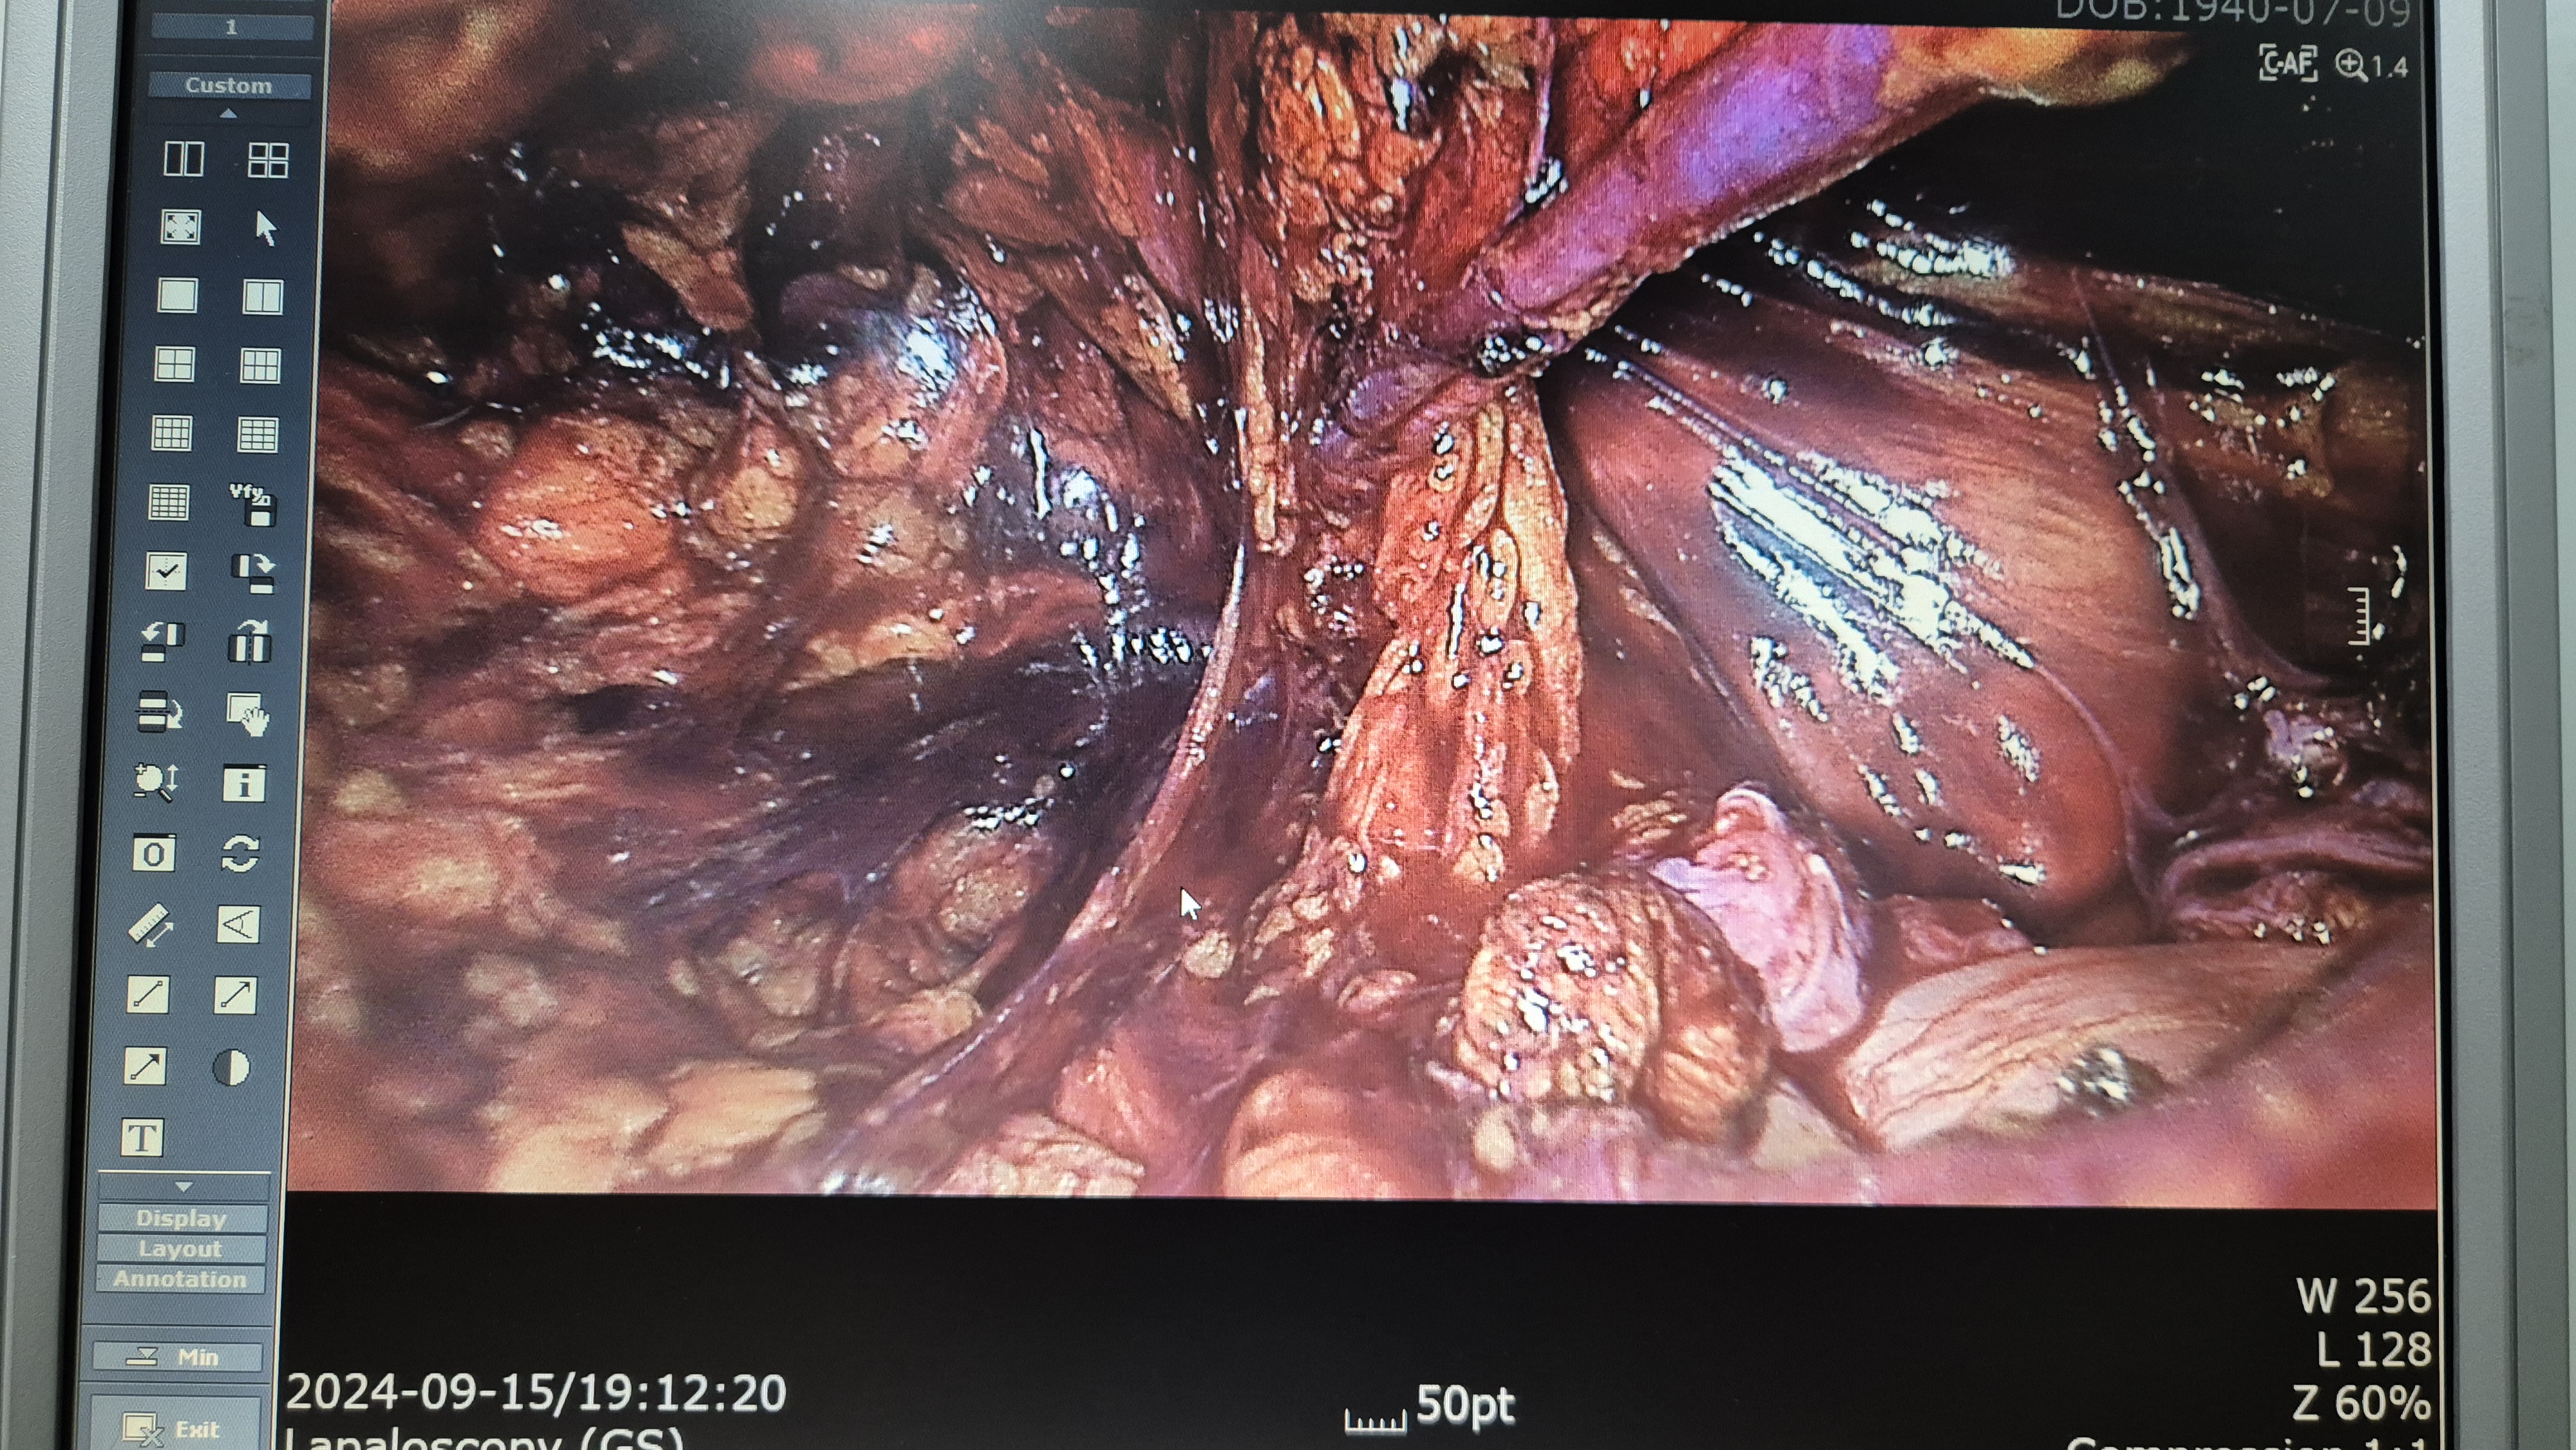

우측 서혜부 종물 주소로 응급실에서 진료보신 분으로 감돈 서혜부 탈장으로 확인되어,

방금 복강경 탈장교정술을 시행했습니다.

수술은 25분 걸렸습니다.